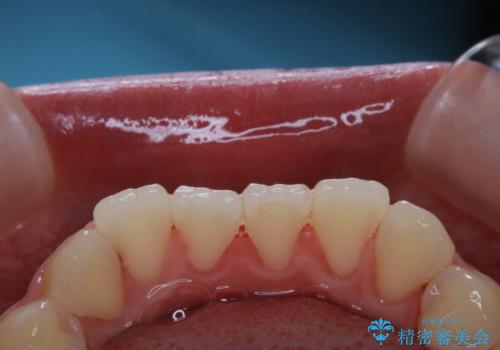

歯面がバイオフィルム(細菌の塊)や歯石で覆われていました。

PMTC(自費クリーニング)で、専門的な器具を使用し、歯石を砕き、バイオフィルムを剥がし、トリートメントまで行いました。歯肉が腫れていたため、バイオフィルムや歯石を取り除いたことにより、施術後の歯肉から出血が見られます。ただし、出血は次第におさまります。

PMTC(自費クリーニング)はホワイトニングではないため、歯が白くなることはありませんが、徹底的に汚れを除去しますので、ご自身本来の歯面となり、艶がでて明るい印象となります。